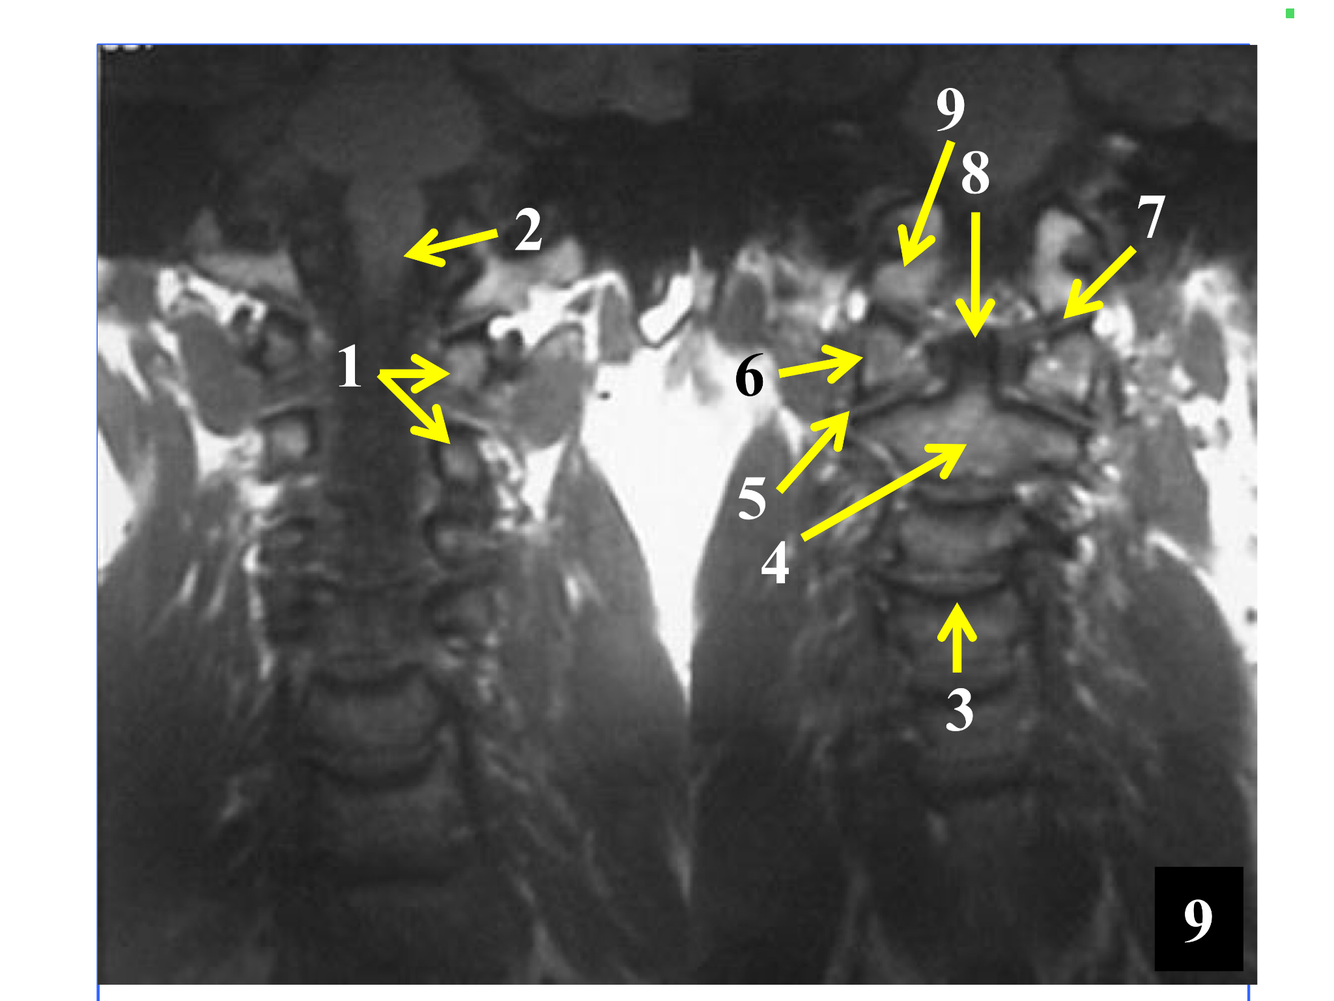

**10. Rt & Lt vertebral arteries**